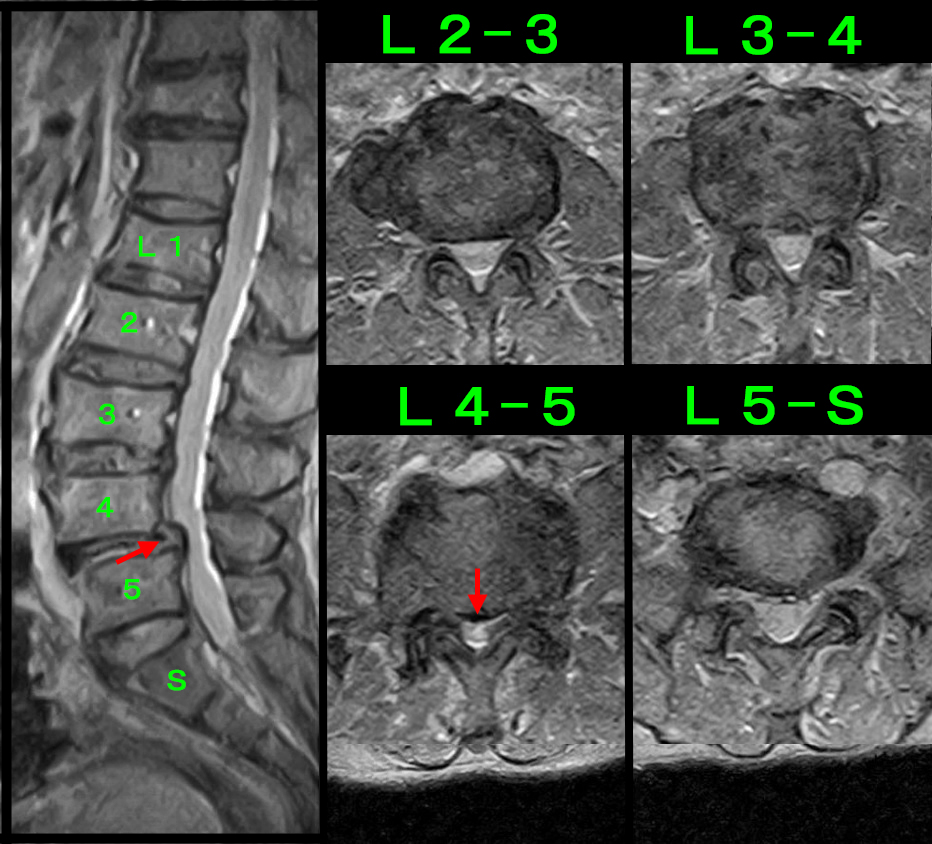

腰椎のMRI検査では、L4-5で脊髄の圧迫の所見が認められ、そこで障害されている左L5神経根にブロックを行い、症状の軽減がえられました。

腰に起因する左坐骨神経痛と判断し、腰椎MRI検査ではL4-5の脊髄の圧迫が平成25年4月の時より悪化していました。やはり左L5神経根ブロックを施行して、左のふくらはぎ痛は軽減し、翌日の法事も問題がなかったと後日教えてもらいました。